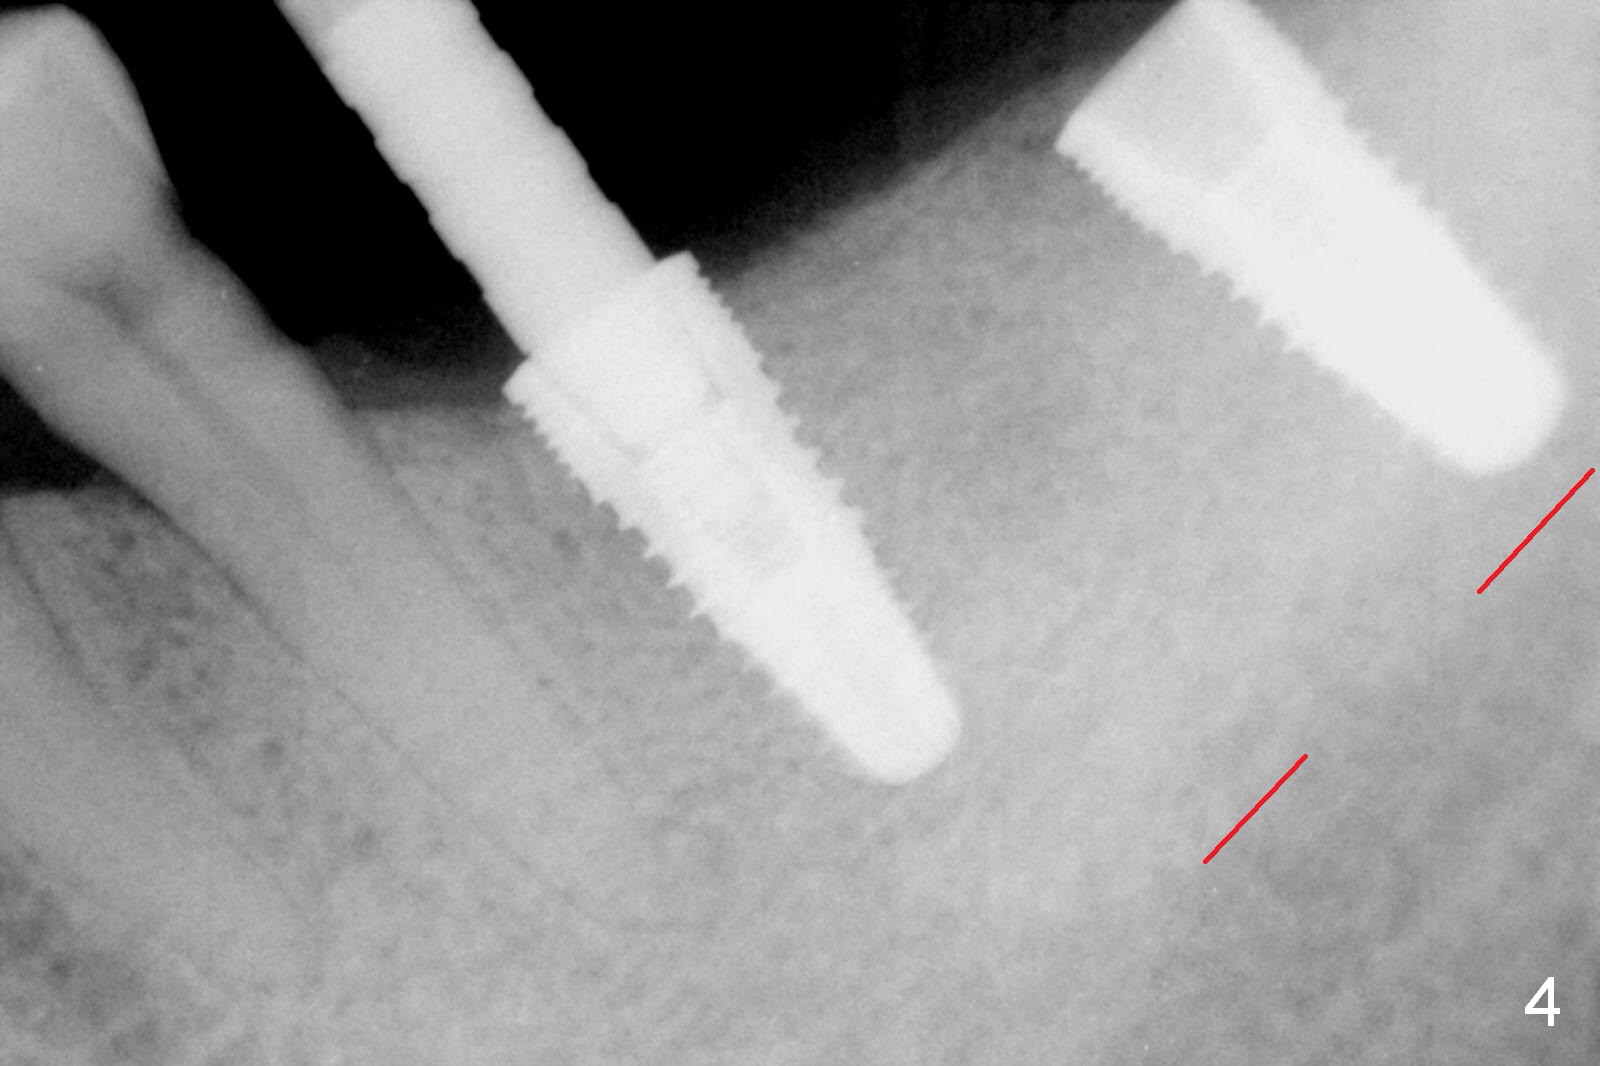

In fact, initial depth for #18 and 19 is 12 mm, quite close to the Inferior Alveolar Canal at #18 (Fig.3 (red dashed line: the superior border of the former). By mistake, the implant at #18 is placed a little deeper than necessary, since the buccal bone is inferior to the lingual one (Fig.4; 5.3x12 mm vs. 5.0x12 mm for #19). As planned, panoramic X-ray is taken immediately postop. Bone height at the 2nd molar decreases drastically as compared to that of the 1st molar, especially on the right side (Fig.5 (abutments: 6.8x5(2) mm for #19, 7.8x5(3) for #18, respectively)). For #30,31 implant placement, initial depth will be 10 and 8 mm, respectively. Follow it faithfully. The implant at #31 could be as large as 5.9 or 6.4 mm to compensate for the length.